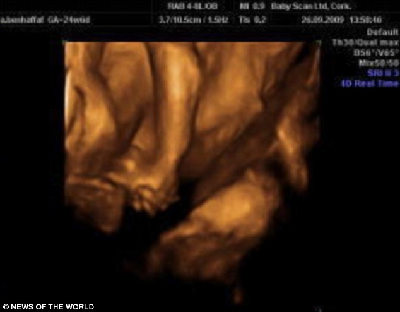

這是連體嬰兒母親懷孕24周的掃描照片,圖中可見胎中嬰兒手牽著手。

據介紹,兩個小家伙于去年12月出生在倫敦大學醫院。早在安琪懷孕12周的時候,B超顯示,她懷上一對連體嬰兒。在24周的時候,則能從B超照片中看出,兩個小家伙的手緊緊握在一起,親密無間的樣子,讓人看了不免動容。